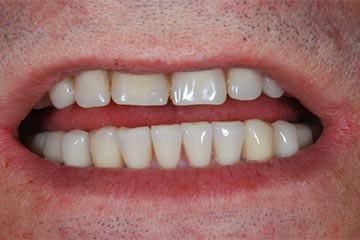

Riabilitazione gnatologica, ortodontica ed estetica

Durata del trattamento: un anno